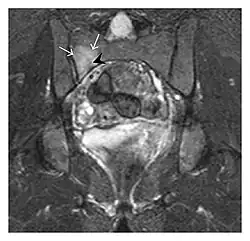

Figure 13: Partial osseous avulsion of the gluteal muscles at the greater trochanter in a 59-year-old man who presented with the right hip pain without a history of trauma. Lauenstein view and anteroposterior and radiographs (not shown) did not show an obvious fracture line or disruption of bony contours in the acetabulum or the right femoral neck. (a) Coronal T1-weighted MRI displays an incomplete fracture line extending partially from the greater trochanter (arrow). (b) Coronal short tau inversion recovery MRI shows heterogeneous hyperintensity in the same region (arrow) as well as hyperintensity within the gluteus medius and minimus muscles (arrowheads) consistent with tissue edema and hematoma.[1]

a -

b